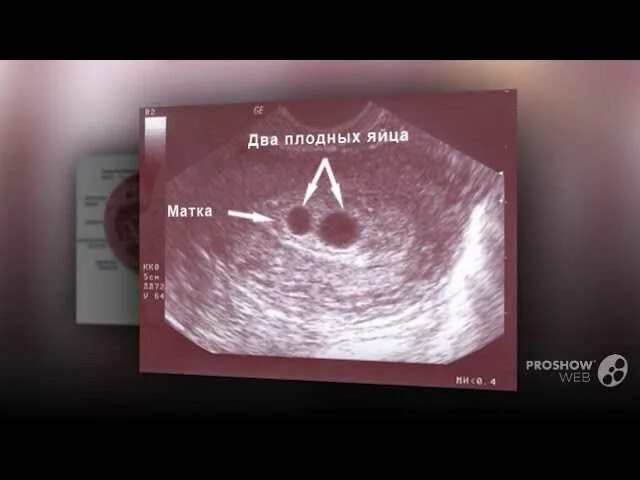

Почему болит яичник при овуляции